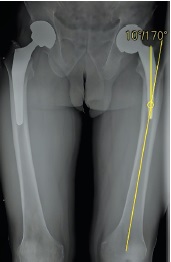

The femoral component was stable, without signs of bone lysis. The component was extracted by traction with a minor effort using an extractor with preliminary use of osteotomes to mobilize it in the proximal part. Its neutral position was registered when assessing the component torsion. Its installation in the retroversion position was revealed during the acetabular component revision, which corresponded to the preoperative X-ray examination findings. The acetabular component was mobilized using an acetabular gouge and removed. The acetabular contours were preserved, without wall defects. The repeated maximum total synovectomy was performed, followed by the use of the Pulsavac (Zimmer) pulse system to remove ceramic fragments using a water jet. Hemostasis control was performed. A mixed fixation femoral component (Alloclassic) and an acetabular press-fit fixation component (Continuum), as well as Ce-Ce tribological bearings (Biolox Delta), were chosen for the revision replacement of the femoral component. A 62-mm continuum acetabular component due to revision arthroplasty, which was fixed with three screws after impaction, and a 62/36 mm ceramic liner, were installed. The femoral component No. 9 (Alloclassic) was installed, considering the correction of the varus position of the previous component with installation along the medullary canal axis. The 36 mm + 7 XL ceramic head was chosen for limb length correction. The femoral component was repositioned into the endoprosthesis cup after the head was installed. Their sufficient volume was revealed when testing movements in the left hip joint. Additionally, the surgical wound was sanitized using the Pulsavac system with 1 L of normal saline solution. Finally, the wound was sutured in layers with Vicryl. Staples on the skin and an aseptic dressing were used. The wound healed by primary intention. The patient was discharged on day 10. The plain radiography of the pelvis in the antero-posterior view determined that the acetabular component inclination was 35°, the femoral component was in the correct position when conducting control 3 months postoperatively, and no valgus or varus angulation was noted (Fig. 6). MSCT in the axial projection revealed that the acetabular component was implanted in the anteversion position of 17° (Fig. 7).

Fig. 6. Anteroposterior X-ray view of the pelvis 3 months after surgery: on the right — a total hip replacement with a cementless proximal fixation (2019); jn the left — a total hip replacement with a cementless proximal fixation